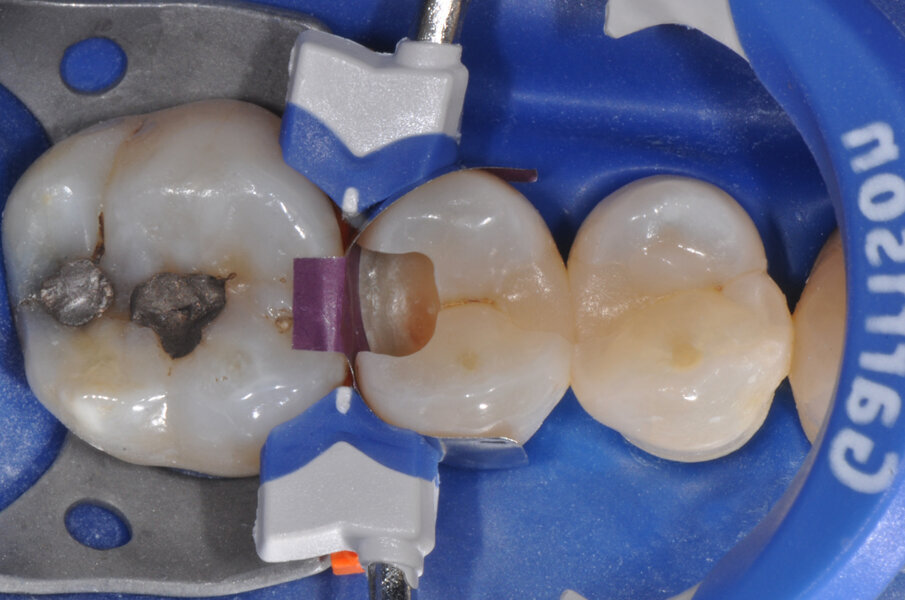

Viene posizionata una matrice Fusion FX175 e inserito un cuneo Fusion FXOR da vestibolare, per favorire la chiusura della matrice nell’angolo tra gradino cervicale e parete assio-pulpare vestibolare, resa difficile dalla rotazione dell’elemento 1.5 (Fig. 6). Si posiziona l’anello separatore FX400 - si noti il perfetto adattamento della matrice alle pareti assiali e al gradino cervicale. Quest’ultimo grazie soprattutto all’azione delle alette in silicone del cuneo (Fig. 7). Un’altra inquadratura evidenzia la profondità della cavità pulita (Fig. 8).